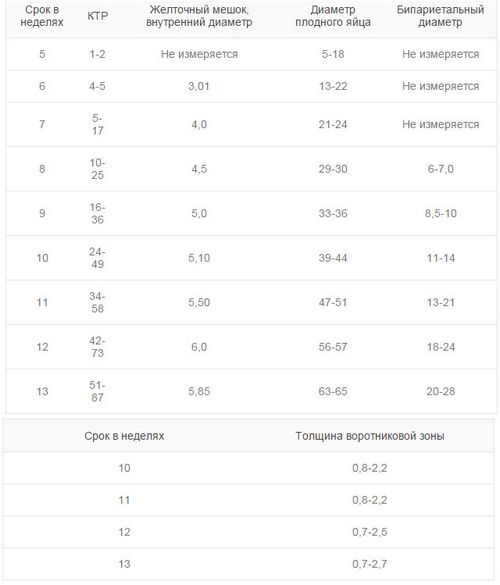

Розшифровка першого УЗД при вагітності (можливо від 10 до 14 тижнів, але найбільш інформативним вважається проміжок між 12 і 13 тижнями) проводиться за кількома показниками.

Куприково-тім'яної розмір - визначається як відстань між головним кінцем плоду і закінченням куприка. У разі нерегулярної менструації, прийнятті протизаплідних препаратів напередодні зачаття цей показник береться за основу визначення терміну вагітності.

Показник окружності голови має найбільшу інформативність у порівнянні з КТР, оскільки активність плода (його рухливість) не завжди дозволяє точно встановити цей критерій. На терміні в 10 тижнів окружність становить 3 см, на 13-14 тижні вже близько 7-8 см.

Частоту серцевих скорочень на першому УЗД необхідно відрізняти від пульсації судин вагітної, тому на цьому терміні показник не має суттєвої діагностичної значущості. Однак по ньому можна визначити аритмію у плода. На терміні в 10 тижнів показник є нормальним при кількості 161-179 скорочень в хвилину, на більш пізніх термінах має місце зниження частоти ударів і до 14 тижня нормою вважається вже 146-168 скорочень.

Воротнікова зона, а точніше її товщина дозволяє припустити розвиток синдромів Дауна або Едвардса у плода. Вчені виявили, що збільшення цього простору підвищує ризик розвитку дітей з хромосомними порушеннями. Під комірним простором розуміють відстань між зовнішньою поверхнею м'яких тканин на шиї плода і внутрішньою поверхнею шкірних покривів. Визначається до 14 тижні.

Дослідження жовтковиммішка дозволяє визначити розвиток вагітності. За його зовнішнього діаметра лікар може зробити висновок про вагітності раннього терміну. Нормою вважається округла форма жовтковиммішка і його внутрішній діаметр в межах 4-6 мм на терміні після 10 тижнів. Також перше УЗД скринінг при вагітності дозволяє визначити його ехогенність (в ідеалі центр його повинен бути гіпоехогенним, а контури - гіперехогенних).

Приблизна таблиця з розшифровкою показань УЗД - все свідчення, крім терміну вагітності, вказані в мм.